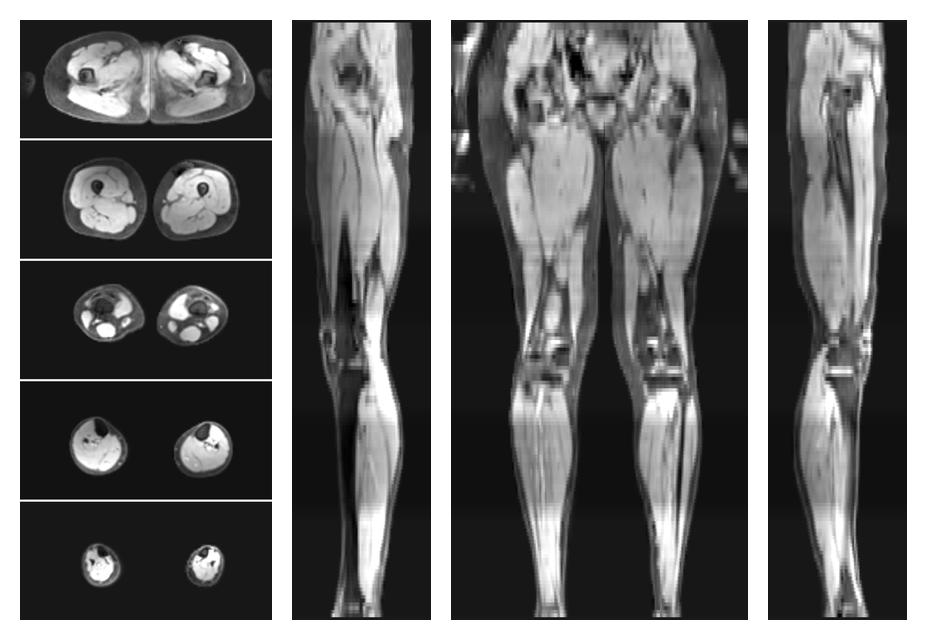

• Water only signal

The water part of the acquired multi-echo spin echo data.